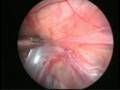

Can this operation done by laparoscopy?

Operation in hernia involves closing of the open passage through which the testis has come down. This can be done from outside as in open surgery or from inside by laparoscopy. If your child has got a hernia on one side, there is a 15 – 25 % chance that he / she may develop a hernia on the opposite side at a later date. With the help of laparoscopy we are able to look at the opposite side to see if the passage is open on that side as well. This can be closed at the same sitting if you wish to. Recovery from surgery, timing of surgery and discharge from hospital are the similar for open surgery and laparoscopic surgery.

Laparoscopic repairs have a slightly higher chance of recurrence (i.e. the hernia coming back again) as compared to open hernias. You can discuss the pros and cons in details with your doctor when you come for consultation.